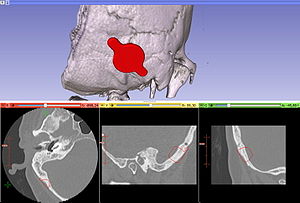

MRI with labeled structures from atlas registered to the CBCT. Registration was carried out with the open source imaging tool 3D Slicer, Version 4.4.0. |